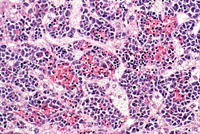

Erythroleukemia is a spontaneous hematopoietic neoplasm of Tg.AC mice characterized by marked hepatomegaly. The affected liver is infiltrated by metarubricytes and less differentiated erythroid precursors.

Examples of erythroleukemia in a Tg.AC mouse.